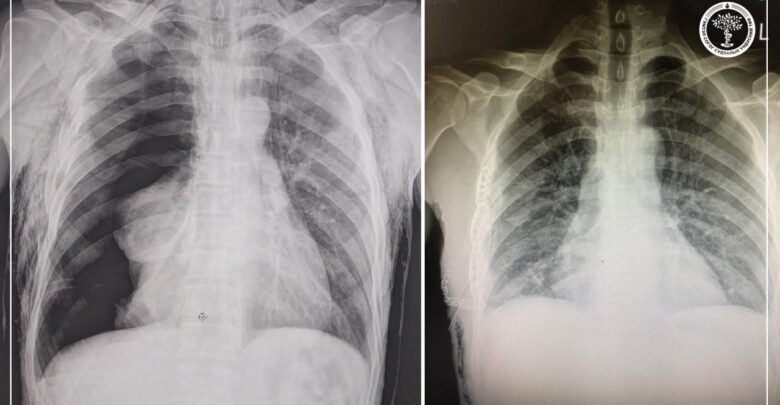

Гэмтэл согог судлалын үндэсний төвийн Хавсарсан гэмтлийн тасгийн эрхлэгч, их эмч П.Баярсайхан, Мэс заслын нэгдсэн тасгийн сувилагч М.Дуламсүрэн нар энэ сарын 09-ний өдөр алсын дуудлагаар Сүхбаатар аймагт ажиллаж, цээжний хөндийн хүнд гэмтэлтэй өвчтөнд мэс заслын яаралтай тусламж үзүүллээ.

Тухайлбал, ГССҮТ-ийн мэс заслын баг бүрэлдэхүүн аймгийн нэгдсэн эмнэлгийн их эмч У.Бямбаа, Ц.Алтансүх, унтуулгийн сувилагч Н.Сугаржав, сувилагч Т.Батдэлгэр, Д.Энхсайхан нартай хамтран дээрх 45 настай өвчтөний хавирганы тогтворгүй хугарлыг бэхлэх мэс заслыг амжилттай хийсэн байна. Өвчтөний биеийн байдал сайжирч, тогтвортой байгаа бөгөөд өдгөө аймгийн нэгдсэн эмнэлэгт мэс заслын дараах эмчилгээ хийлгэж байгаа аж.